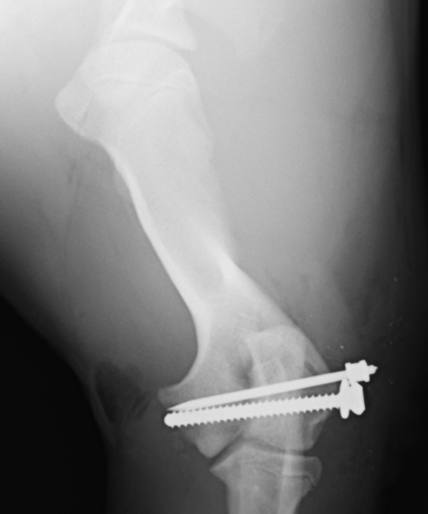

術後のX線画像です。ずれていた骨を太めのスクリューと、細いピンで固定しています。骨折線がわからないレベルまで固定できています。